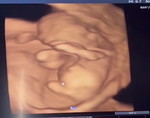

กำลังตั้งครรภ์